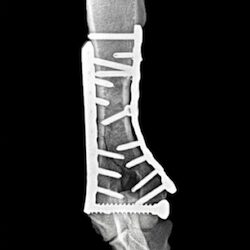

Cutting-edge surgical techniques supported by the latest evidence; TPLO for cruciate ligament tears. Management of patellar luxation, elbow, shoulder, hip & tarsal joint disease, complex fractures & limb deformities.